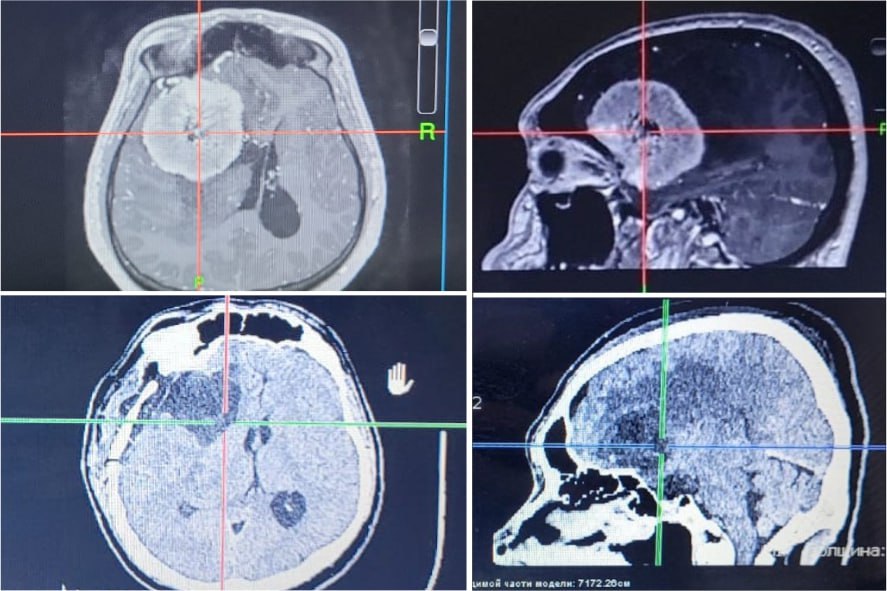

В Новокузнецке в Городскую клиническую больницу №29 имени А.А. Луцика прооперировали мужчину в возрасте 41 года с опухолью головного мозга. Как сообщил министр здравоохранения Кузбасса Дмитрий Беглов, новообразование было размером 6х6 сантиметров.

Также отмечено, что до обращения к врачам его беспокоили сильные головные боли и головокружения. Изначально доктора скорой заподозрили у пациента инсульт, но после обследования у него выявили выраженную менингиому. Докторами было принято решение оперировать пациента.

Операция была сложной, так как через капсулу опухоли проходила среднемозговая артерия. Доктора приложили большие усилия, чтобы не совершить ни одного неверного движения, в противном случае это могло привести к утрате дееспособности пациент.

«Пятичасовая операция прошла успешно. Спустя сутки состояние мужчины значительно улучшилось, а через две недели его выписали из больницы без признаков неврологического дефицита. Новокузнечанин уже вернулся к привычной жизни»,- отметил министр здравоохранения Кузбасса.